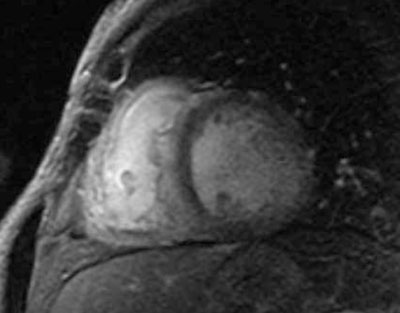

En la RM, debido a la expansión intersticial causada por el depósito de amiloide, la retención de gadolinio (Gd) da lugar a un realce tardío (RT) y un score QALE (Query Amyloid Late Enhancement) elevado. El score QALE es una escala semicuantitativa de RT que asigna hasta 4 puntos al ápex, base, mitad del VI y VD. Un score QALE ³14 tiene sensibilidad de 82% y especificidad de 76% para el diagnóstico de amiloidosis, pero tampoco logra diferenciar con certeza entre los subtipos AL y ATTR7.

Paciente masculino de 75 años, sin antecedentes de cardiopatía, hipertenso, dislipidémico e hipotiroideo, con cuadro de disnea progresiva. En el ECG se observa ritmo sinusal de 63 cpm, P y PR normales, con bloqueo completo de rama derecha, hemibloqueo anterior izquierdo y alteraciones difusas de repolarización, sin minivoltajes (Figura 1). El eco Doppler mostró severo engrosamiento del VI, hipocontractilidad global más marcada en pared anterior, fracción de eyección del ventrículo izquierdo (FEVI) de 30% y disfunción diastólica severa, configurando un patrón de miocardiopatía hipertrófica (Figura 2). Con este resultado se realiza RM que informa, en secuencia de RT, imposibilidad de anulación del miocardio con diferentes tiempos de inversión, compatible con la presencia de amiloidosis. Presenta además RT del VD, con QALE score de 12 (Figura 3). Dada la disnea aparentemente desproporcionada, se realiza centellograma de perfusión miocárdica con 99mTc-sestamibi con estrés farmacológico para descartar componente isqué mico, que no demuestra alteraciones de la perfusión y FEVI <50% (Figura 4).